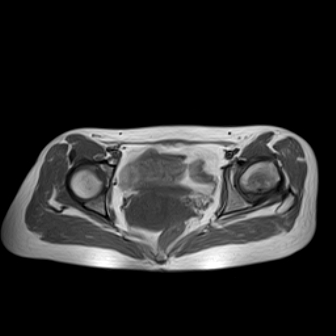

请看看我的片子,我得的什么病,该怎么治疗?谢谢[img][/img]

片子不全,应该是左侧股骨头无菌坏死,右侧似乎没问题,到正规医院治疗,千万别看广告去小医院,吃中药什么的,都是骗人的(说了也白说,百分百都得让人骗点钱才甘心。)

应该是左侧股骨头无菌坏死